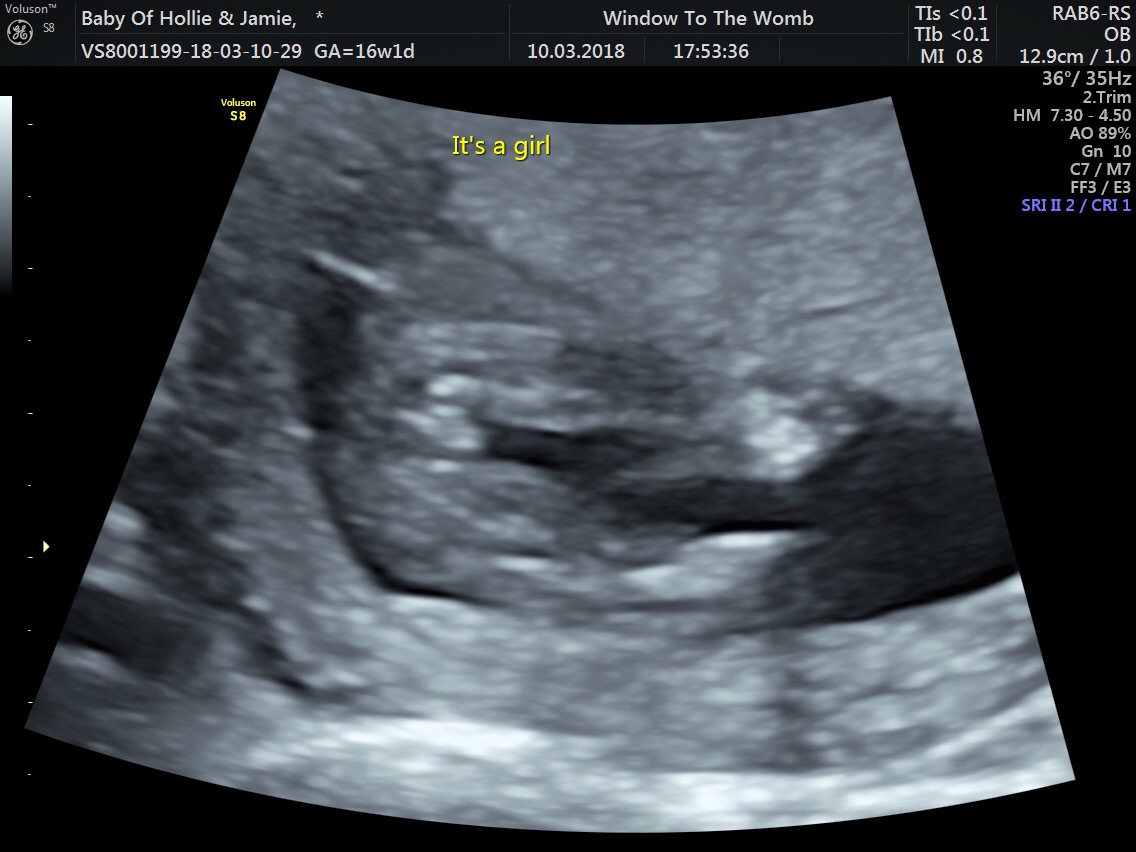

This is a girl right?

I have always dreamed of having a daughter and to be told my first child is one has truly made me happy. We had an early scan at 16W 1D but my partner is having doubts. I want to begin buying clothes and sharing my joy but our NHS scan isn't for another 3 weeks. What do you think and why do you think it? I am new to all this :)

I woukd say yes, I can see "the hamburger" :-)

Yes I agree with Linni I believe i'm seeing the 3 lines/hamburger :) I have circled the area we would all be looking at :)

Looks like a girl to me. Congrats! [emoji166]